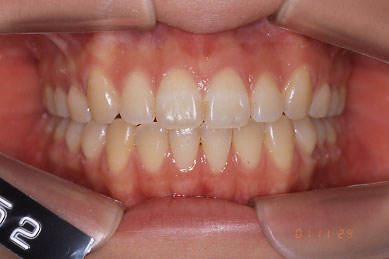

After右側貌

Before

Afterリボン歯科・矯正歯科グループは、インビザライン矯正の高精度、スピーディ、快適な治療の為にiTero(口腔内スキャナ)をグループで18台導入しております。